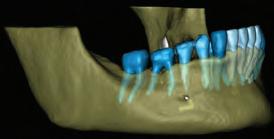

Figure 3a-c: 3D Imaging of the patient’s jaw and teeth. The volume of the CBCT imaging was segmented to STL models, and then the mandible model was made semitransparent to show the IAN canal pathway. (The 3D models were segmented with Diagnocat (Diagnocat Inc., USA) and displayed in the Exocad Webview software (available for free use at webview.dental).

A 31-year-old woman presented with cosmetic concerns regarding her smile and requested a conservative enhancement. After clinical and radiographic analysis, digital 35mm photographs were taken and reviewed by the restorative clinician, technician, and surgeon (Fig 1). A digital impression was taken of the maxillary and mandibular arches using an intraoral scanner (Trios 3, 3Shape; Fig 2), and a smile design was developed with NemoSmile Design 3D software (Nemotec; Fig 3a). This allows for a facially driven smile frame to be created using reference lines of facial and smile proportions and natural teeth shapes and textures from the digital library (Fig 3b).

After developing the simulated mock-up, a 3D-printed resin model was created using CAD software (Fig 4a), and a clear PVS matrix (Exaclear, GC America) was fabricated to replicate the printed diagnostic wax-up using a nonperforated tray (Fig

Fig 1 Preoperative clinical views of a 31-year-old woman presenting with diastemas and limited tooth visibility. (top) Portrait. (center row) Intraoral views. (bottom row) Smile.

4b). This matrix was used to create an intraoral motivational mock-up with bis-acryl composite (Luxatemp Ultra, DMG). This additive mock-up provides the interdisciplinary team with an intraoral translation for evaluation (Fig 5). Upon evaluation of the digital smile frame and the clinical translation, it was determined that multiple esthetic and restorative requirements were necessary for an optimal biologic framework, and the interdisciplinary team determined the best sequence for these procedures. The patient was presented with the interdisciplinary treatment possibilities that included restoring the maxillary anterior teeth and premolars with a minimally

invasive preparationless procedure or with less conservative veneer preparations. The restorative materials discussed included injectable resin composites and ceramic (ie, feldspathic, pressable, machinable). For an optimal biologic framework and health, it was determined that connective tissue grafting would be necessary for treatment of the recessiontype defects on the maxillary left central and lateral incisors, canine, and premolars. The patient opted for the conservative preparationless composite veneers using the injectable resin technique followed by a connective tissue surgical procedure using the tunneling technique.

Fig 2 Digital scan of the preoperative maxillary arch.

Fig 3 (above) Simulated smile developed with NemoSmile Design 3D software. (left) A facially driven smile frame was created using reference lines of facial and smile proportions and natural teeth shapes and textures from the digital library.

Fig 4 (left) A 3D-printed resin model was created using CAD software. (right) A clear PVS matrix (Exaclear, GC America) was fabricated to replicate the printed diagnostic wax-up using a nonperforated tray.

Fig 5 (left) The clear PVS matrix was used as a transfer vehicle for the bis-acryl composite (Luxatemp Ultra). (center and right) This additive mock-up provides the interdisciplinary team with an intraoral translation for evaluation; this is an excellent method for increasing the patient’s understanding of the planned clinical procedure and the anticipated final result.